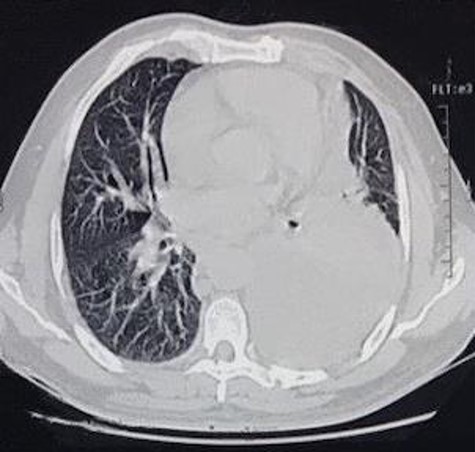

The first case consists of a 26-year-old male that presented with dyspnoea at rest, tachycardia, jugular vein distention, and slight facial and upper limb edema. The patient had been previously treated with ceftriaxone and moxifloxacin, and underwent a left thoracostomy due to a chest radiograph that showed a pleural effusion in the left inferior hemithorax. At auscultation, the patient had reduced air entry in the left lung base. The patient did not show improvement with the treatment previously given, so new laboratory tests were ordered. The blood test showed an elevated lactate dehydrogenase at 652 U/L and the pleural fluid analysis showed an elevated lactate dehydrogenase at 911 U/L, cholesterol level at 46 mg/dl, and triglyceride level at 847 mg/dl. According to these results, the pleural effusion was classified as an exudate. The high triglyceride level was consistent with a chylous effusion. A chest CT confirmed a pericardial effusion, the previously noticed free pleural effusion, and an irregular mass in the anterior mediastinum with heterogeneous density that included hypodense areas that suggest necrosis (Figs 1 and 2). Subsequently, the patient underwent surgical treatment, which consisted of a pericardial window. Aside from this procedure, the anterior mass was biopsied. Histological analysis revealed a non-Hodgkin lymphoma. Due to the diagnosis, the patient was transferred to the hematology care unit to receive chemotherapy, but he continued to deteriorate and passed away 2 months later.

CT scan axial view of anterior mediastinal mass, left lung free pleural effusion and intercostal drainage.